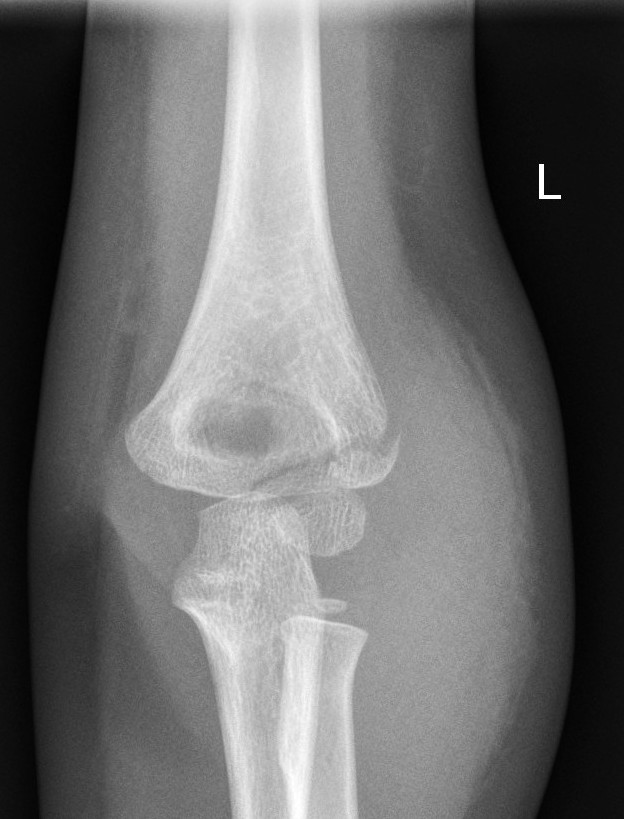

Lateral condyle fractures

- All lateral condyle fractures should be discussed with the Orthopaedic team for further management. They are generally unstable and prone to displacement and often require operative fixation.

Lateral condyle fracture